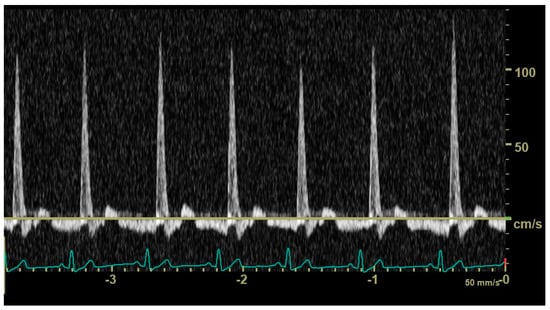

In diastole, when the aortic segment caudal to the renal artery is imaged, a triphasic flow pattern is expected in healthy subjects, characterized by an initial negative deflection followed by a positive rebound and a third phase referred to as end-diastolic flow [21]. Based on the direction of the end-diastolic flow, abdominal aortic flow patterns were classified as one the following three types: antegrade when blood flowed caudally at the end of diastole (Figure 1); absent when no blood flow could be detected at the end of diastole (Figure 2); retrograde when blood flowed cranially at the end of diastole (Figure 3) [11].

Figure 3. Pulsed_wave Doppler ultrasonography of abdominal aortic flow in a dog with left-to-right patent ductus arteriosus showing a retrograde end-diastolic flow.